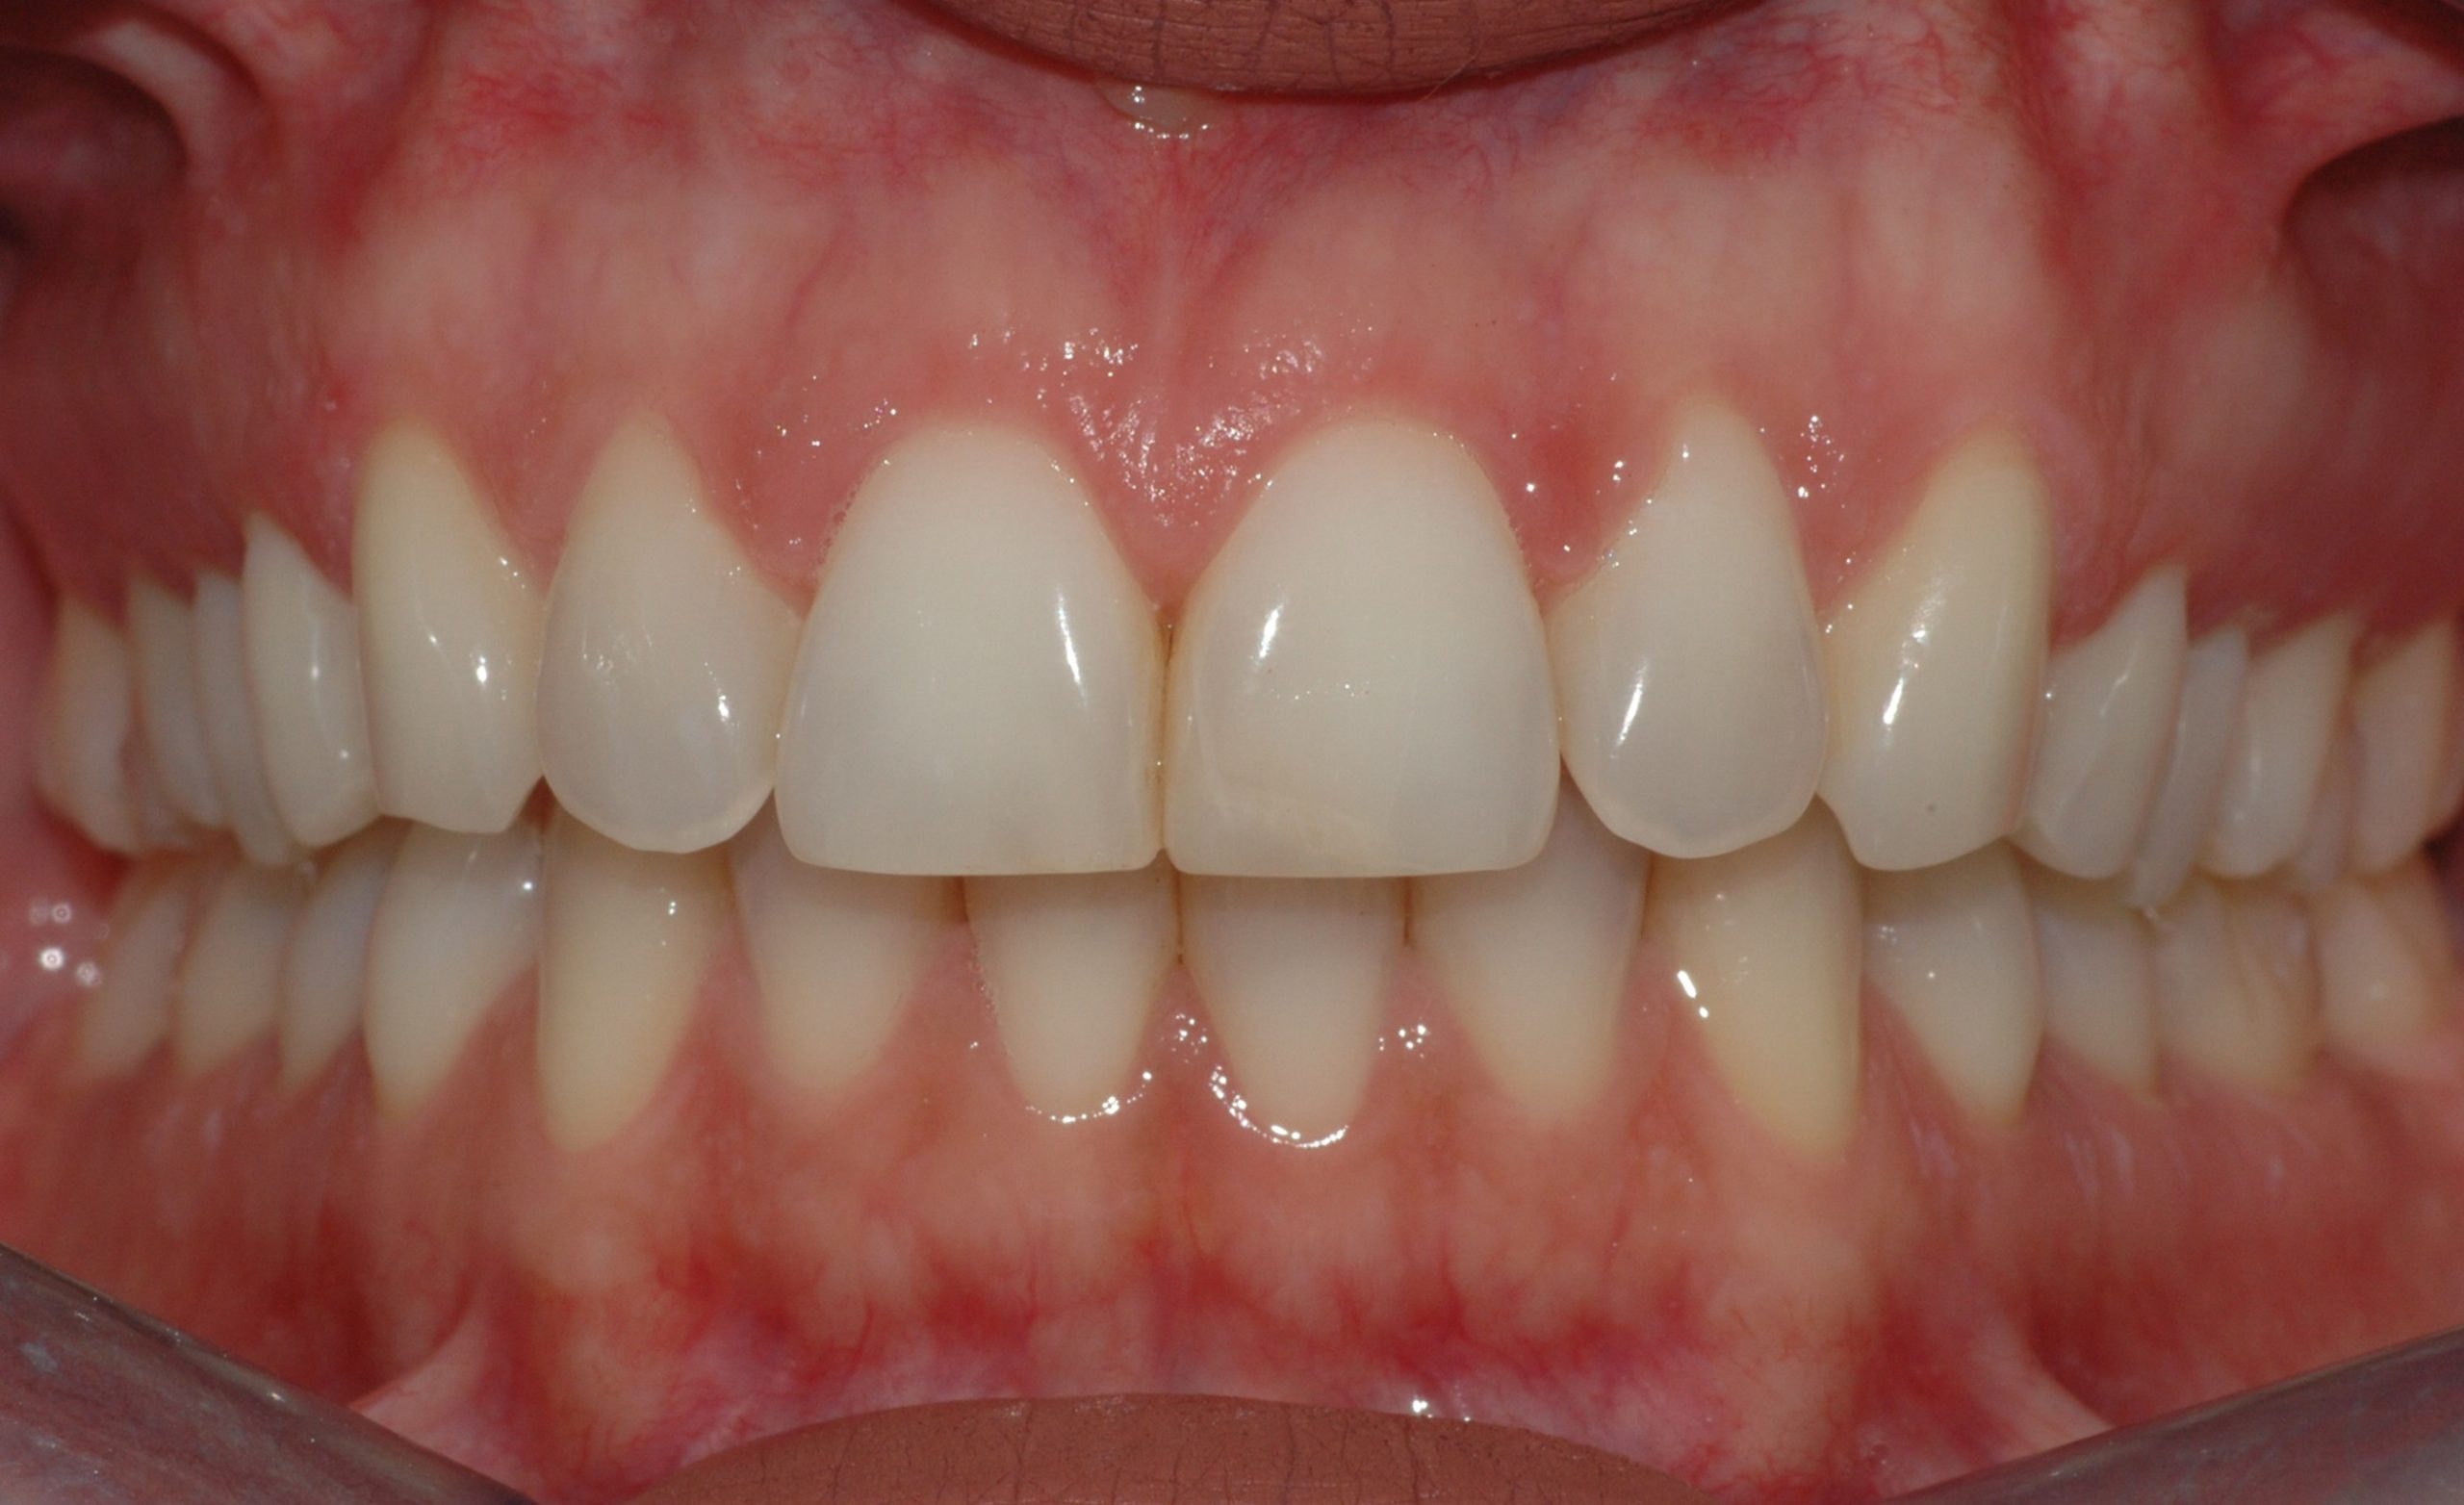

Caso clinico

La paziente si presenta con la richiesta di chiudere il diastema presente tra gli incisivi superiori, sia per motivi estetici, sia a causa di una forte infiammazione gengivale provocata dall’intasamento alimentare (food impaction) nello spazio aperto. In 6 mesi di tempo, il trattamento tramite allineatori, ha chiuso lo spazio e risolto il problema a livello gengivale.

PRIMA

DOPO